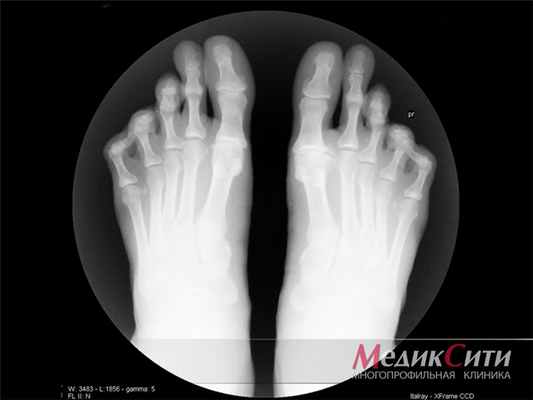

Наиболее распространенным проявлением подагры является острый моноартрит, характеризующийся внезапной сильной болью и отеком. Однако могут поражаться сразу несколько суставов – обычно первый плюснефаланговый, предплюсне-плюсневый, голеностопный и коленный суставы. Они становятся теплыми на ощупь, опухшими, кожа над ними гиперемированная (покрасневшая). Значительная боль в суставах ограничивает диапазон движения. Могут определяться жесткие подкожные узелки (тофусы) над разгибательной поверхностью сустава, на дорзальных (задних) поверхностях рук и ног, в ушной раковине. При тяжелом течении повышается температура тела. Приступ обычно длится несколько дней, реже - нескольких недель. После приступа деформации сустава не возникает.

Это острый приступ артрита, как правило, одного сустава, чаще I плюсне-фалангового, голеностопного или коленного. Обычно приступ артрита развивается ранним утром или ночью, среди полного здоровья. Проявляется он в виде сильной давящей боли в том или ином суставе. Пораженный сустав опухает, повышается температура в области сустава, кожа краснеет и начинает лосниться. Обычно днем боль становиться меньше, но к ночи она снова усиливается. Продолжительность приступа подагры длится от двух-трех дней до недели, иногда и больше. При повторном приступе в такое воспаление могут вовлекаться и другие суставы. При длительном течении подагры на сгибательных поверхностях суставов образуются тофусы, которые могут вскрываться с выходом кристаллов мочевой кислоты. В этот момент пациент испытывает довольно интенсивную боль.

Нарушение так называемого пуринового обмена приводит к повышению концентрации мочевой кислоты в крови и моче, образованию уратных кристаллов и их отложению в мягких тканях, в том числе в области суставов верхних и нижних конечностей. Со временем отложения кристаллов мочевой кислоты (ураты) формируют узелковые подкожные образования - тофусы, которые хорошо видны невооруженным глазом и позволяют врачу поставить диагноз даже при обычном внешнем осмотре. Однако задолго до образования тофусов болезнь проявляет себя приступообразным, необычно тяжелым воспалением суставов - подагрическим артритом (чаще всего располагающимся в области большого пальца стопы, хотя возможно поражение других суставов, чаще ног).

Клиническая картина

Классический острый приступ подагры возникает внезапно, как правило, ночью на фоне хорошего общего здоровья. Развитию приступа обычно предшествуют события, предрасполагающие к резкому повышению уровня мочевой кислоты к крови – фуршеты, дни рождения, застолья с обильным употреблением мясных продуктов. Последние, как известно, нередко используются в качестве закуски после приема алкогольных напитков. Сочетание этих факторов крайне неблагоприятно, поскольку алкоголь ухудшает выведение мочевой кислоты с мочой, что быстро приводит к «скачку» мочевой кислоты в крови и созданию необходимых условий для развития подагрического артрита. Еще одним фактором, предрасполагающим к обострению или возникновению приступа суставной подагры, является обезвоживание организма, что нередко случается при обильном потоотделении после посещения бани или сауны. Спровоцировать начало обострения подагры могут также переохлаждение и травма, в том числе незначительная травма, например, ношение тесной обуви. Приступ подагры достаточно однотипен: возникает чрезвычайно интенсивная боль в 1 плюснефланговом суставе (сустав большого пальца), он резко опухает, становится горячим и красным, а затем сине-багрового цвета. Функция сустава нарушается, больной не может даже пошевелить пальцем.

Если подагрический артрит переходит в хроническую форму, то это приводит к деформации суставов и нарушению их функции.